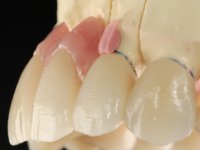

Perante a situação clínica apresentada, foi proposta uma reabilitação oral que melhorasse a aparência estética, mas que também solucionasse a falta de dentes posterior, procurando uma reabilitação funcional e estética. Foi proposta a substituição da ponte metalo-cerâmica por uma ponte com infraestrutura em zircónio, revestida a cerâmica coronária e gengival. A zona edêntula do primeiro quadrante seria reabilitada com 2 implantes e uma ponte de dois elementos. Pretendia-se com este plano de tratamento recuperar a dimensão vertical da oclusão e reformular a anatomia dentária, criando uma aparência estética mais natural.

Foram realizadas impressões em alginato a ambas as arcadas, acompanhadas pelo registo das relações inter-maxilares e recolha de informação com arco facial. No laboratório foi confecionada uma ponte provisória de 13 elementos em acrílico autopolimerizável na qual foi incorporado um reforço metálico. Os dentes 1.7/1.4/1.3/2.2/2.3/2.4 e 2.6 foram utilizados como pilares. A ponte metalo-cerâmica foi removida após a realização de cortes longitudinais feitos com brocas diamantadas. Os preparos dentários foram re-preparados e a ponte provisória foi rebasada em boca com acrílico auto-polimerizável. Após a confeção da ponte provisória, foi confecionada uma epítese gengival em resina composta com tonalidade gengival, com o objetivo de funcionar como uma maquete, que permitisse à paciente pré visualizar a possibilidade de utilização de cerâmica de tonalidade gengival no trabalho final. Esta opção foi aprovada como válida pela paciente. Posteriormente foi planeada e executada a colocação de dois implantes no primeiro quadrante. O monobloco provisório foi retirado para a colocação dos implantes e após a cirurgia foi novamente cimentado provisoriamente. Passado o período de osteointegração foram realizadas as impressões ao maxilar superior. Na zona anterior foram utilizados fios de afastamento gengival impregnados e nas zonas posteriores foi utilizada pasta de caolino. A impressão aos implantes utilizou a técnica de moldeira aberta. O material de impressão utilizado foi o silicone de adição putty soft e regular, ambos de presa rápida. No laboratório, o modelo das restaurações provisórias e a maquete em resina serviram de orientação ao enceramento da infra-estrutura. O modelo de trabalho em gesso e o enceramento da infraestrutura foram colocados num scanner laboratorial e deram origem a um modelo de trabalho digital no qual foi sobreposta a digitalização da infraestrutura encerada. Esta sobreposição facilitou o desenho CAD da infraestrutura em Zr. Posteriormente, o desenho CAD por um processo CAM de fresagem deu origem às peças de Zr. A infraestrutura foi pigmentada com uma coloração rosada, que favorecesse a colocação posterior de cerâmica de tonalidade gengival. Durante a modelação da infraestrutura foi detetada a necessidade de aumentar o desgaste oclusal no dente 1.4. Este desgaste foi feito no modelo de trabalho real e foi confecionada uma guia de controlo de desgaste em acrílico que acompanhou a prova das infraestruturas. Em boca foi realizado o desgaste corretivo e foi realizada a prova das peças de Zr. Durante a prova foi reavaliada a escolha da cor da cerâmica de tonalidade gengival. O tratamento foi finalizado no laboratório e após aprovação pela paciente foi colocado definitivamente em boca.